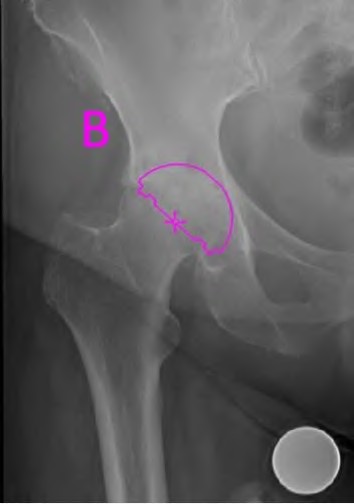

A 45-year-old female with developmental dysplasia of the hip (DDH) presents for THA. Preoperative radiographs show the femoral head is subluxated, with 80% proximal migration relative to the height of the normal true acetabulum. Based on the Crowe classification, what type of dysplasia does she have?

Explanation